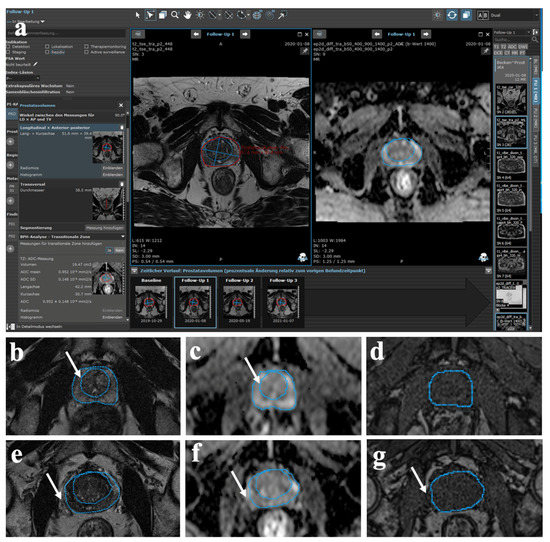

2.4. Semi-Automatic MR Image Analysis